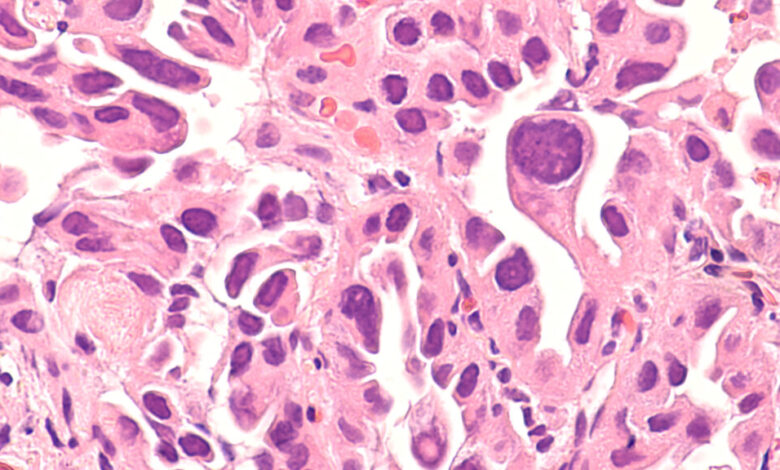

The shifting landscape of lung cancer demographics is shedding light on the importance of recognizing and addressing the unique challenges faced by never-smokers who develop the disease. From the different risk factors involved to the particular mutations found in these cases, understanding the nuances of lung cancer in non-smokers is crucial for improving outcomes and tailoring treatment strategies.

As researchers delve deeper into the reasons behind the rise in lung cancer cases among never-smokers, factors like air pollution, radon exposure, and genetic predispositions are coming into focus. By pinpointing these risk factors and developing targeted screening programs, there is hope for better detection and management of lung cancer in this population.

Ultimately, the goal is to bridge the gap in lung cancer care for never-smokers and ensure that all individuals at risk have access to timely and appropriate screening and interventions. By staying vigilant and proactive in addressing the changing face of lung cancer, we can work towards reducing the burden of this deadly disease on individuals and communities worldwide. As an individual of Asian descent or someone who grew up in an area with high levels of air pollution, you may be at a higher risk for certain health conditions. This could be due to genetic factors or environmental exposures that have impacted your health over time. Additionally, if you have a job that puts you at risk, such as working long hours in a kitchen, it’s important to consider screening options, especially if you are over the age of 60.